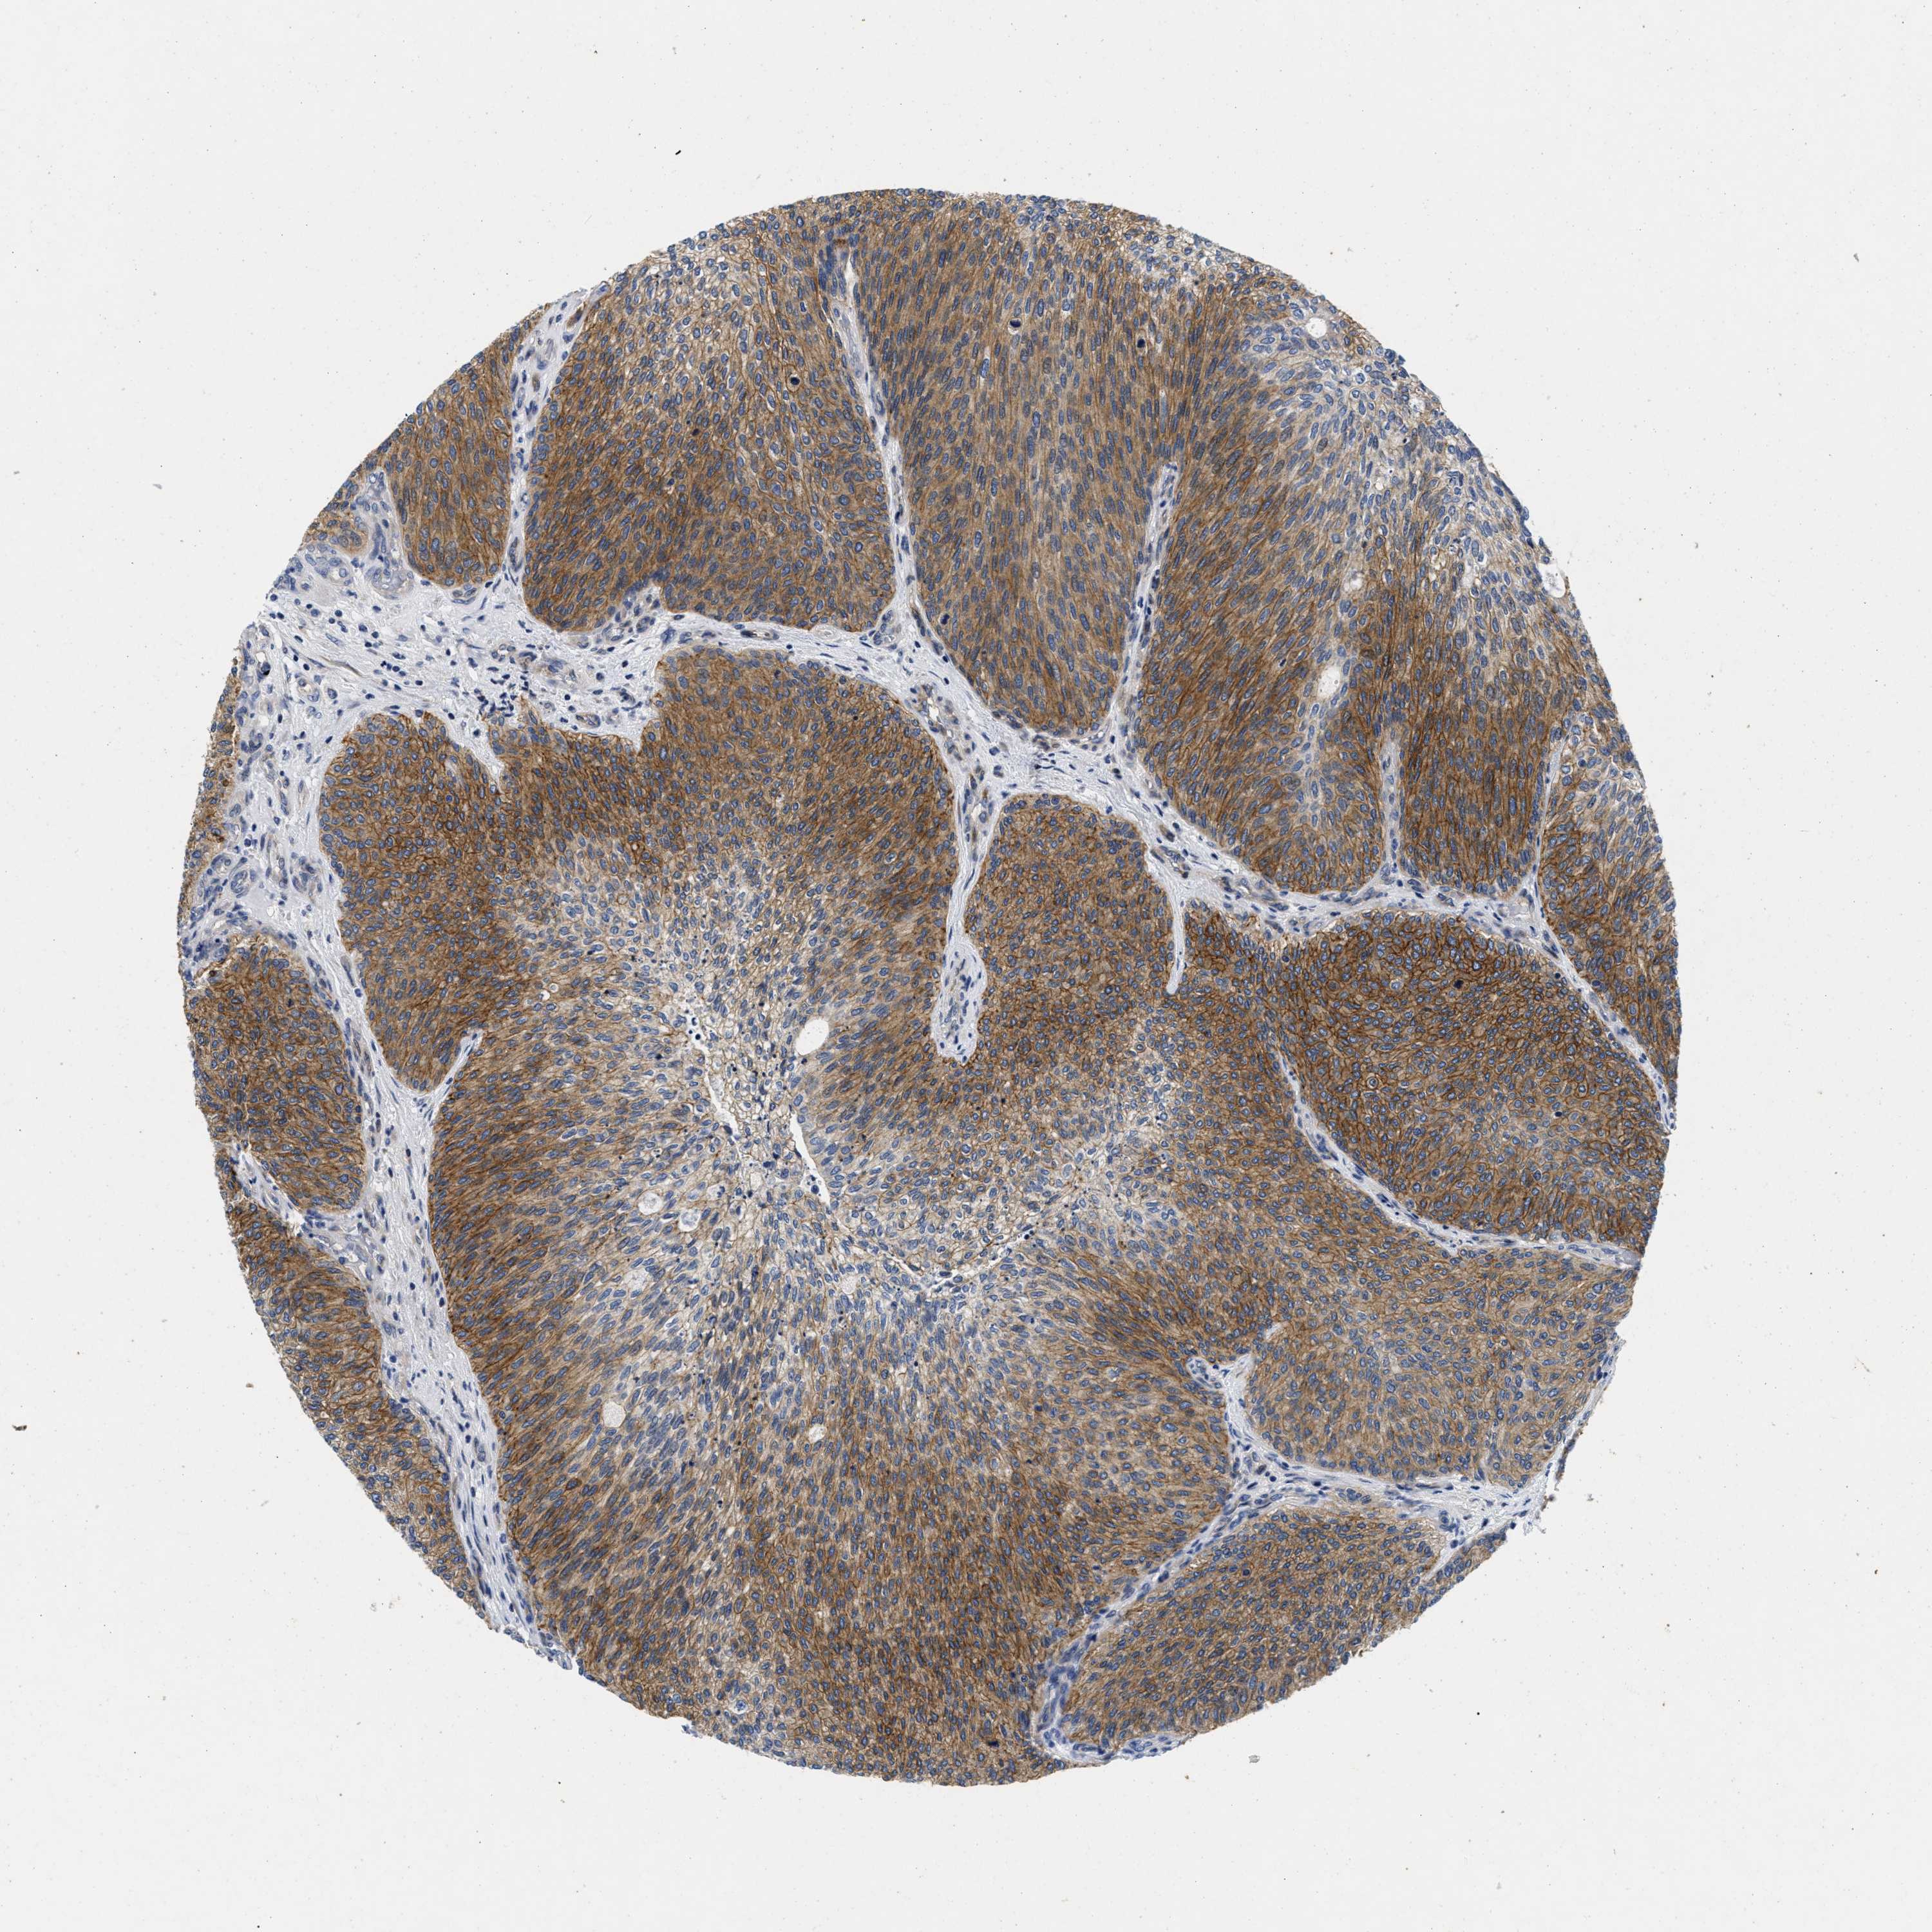

UROTHELIAL CANCER - Protein expressioni

A mouse-over function shows sample information and annotation data. Click on an image to view it in a full screen mode. Samples can be filtered based on level of antibody staining by selecting one or several of the following categories: high, medium, low and not detected. The assay and annotation is described here.

Antibody stainingi

Antibody staining in the annotated cell types in the current human tissue is reported as not detected, low, medium, or high, based on conventional immunohistochemistry profiling in selected tissues. This score is based on the combination of the staining intensity and fraction of stained cells.

Each image is clickable and will lead to virtual microscopy that enables deeper exploration of all samples and also displays staining intensity scores, fraction scores and subcellular localization as well as patient and tissue information for each sample.

Antibody HPA007256

Antibody HPA028732

Staining

High

Medium

Low

Not detected

Intensity

Strong

Moderate

Weak

Negative

Quantity

>75%

75%-25%

<25%

None

Location

Nuclear

Cytoplasmic/membranous

Cytoplasmic/membranous,nuclear

Urothelial carcinoma, Low grade

Urothelial carcinoma, High grade